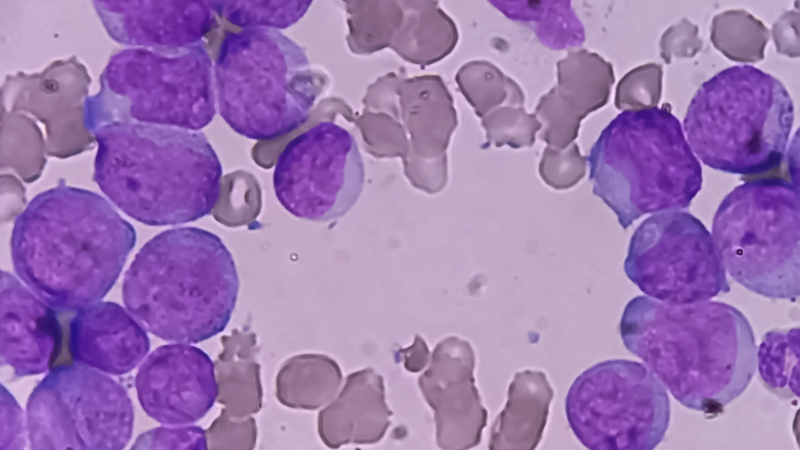

Avances en la Inmunofenotipificación de LMA

La leucemia mieloide aguda es una neoplasia hematológica ...